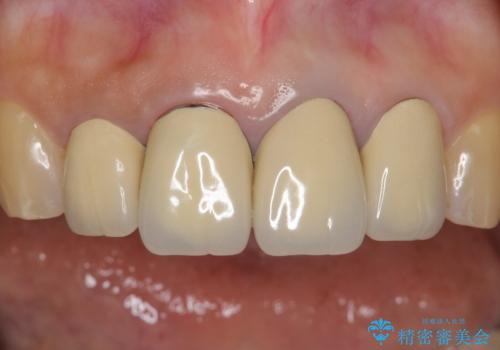

- 前歯のセラミック治療から5年経過した患者様です。

数年ぶりにメンテナンスに来て下さいました。

治療した上の前歯4本は全く問題がないそうで、「どうしてこんなに長持ちするんですか?」と聞かれた程です。

5年前のクラウン装着時と比較したところ、歯肉が成熟し歯間乳頭ができており、より天然歯のように自然に見えました。

患者様の良好なセルフケアと精密な適合の良いクラウンにより、歯肉の腫脹や退縮も認められませんでした。